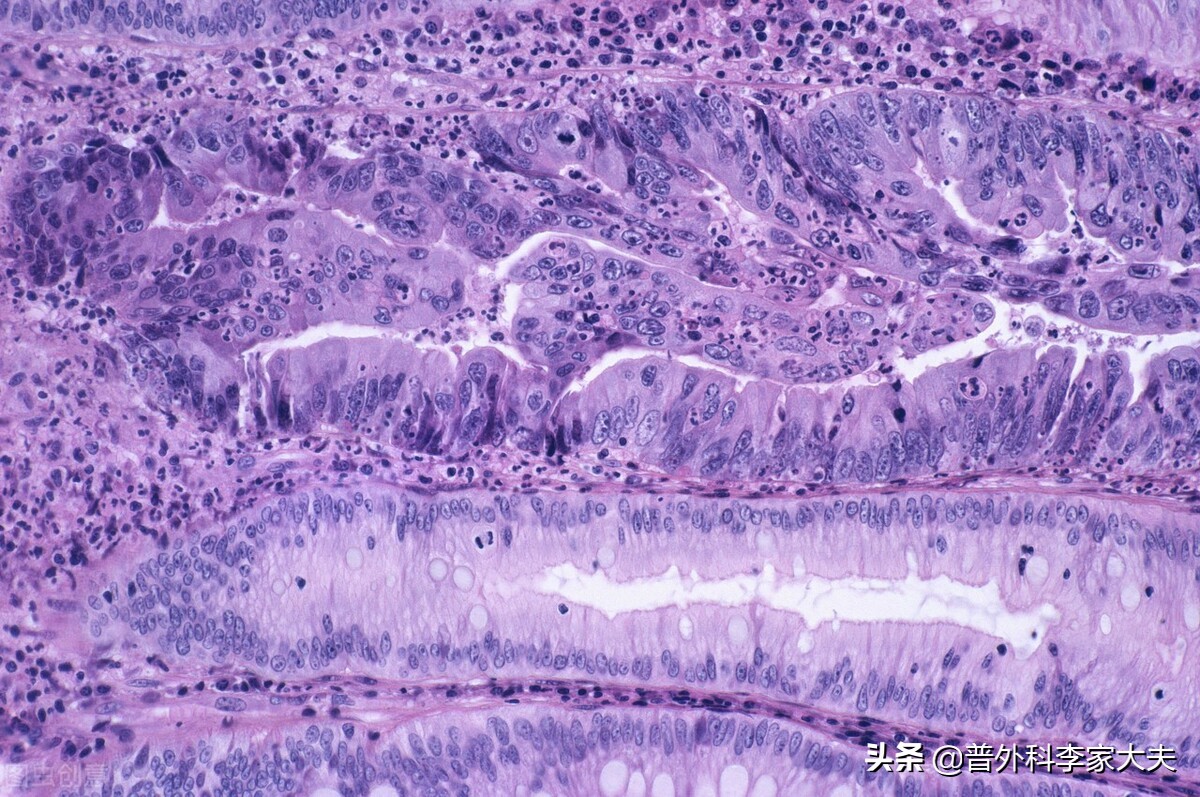

上述结论,还是未考虑患者的直肠癌组织学类型与分子分型得出的。如果患者是病理组织分类很差的直肠癌,比如是对化疗敏感性不好的粘液癌或印戒细胞,则术后不做放疗来防治直肠癌复发,简单就是拿自己生命开玩笑。如果患者是对化疗与靶向治疗均不敏感的直肠癌分子分型,则术后的辅助放疗,几乎可以说是患者防治直肠癌复发的最好选择了。